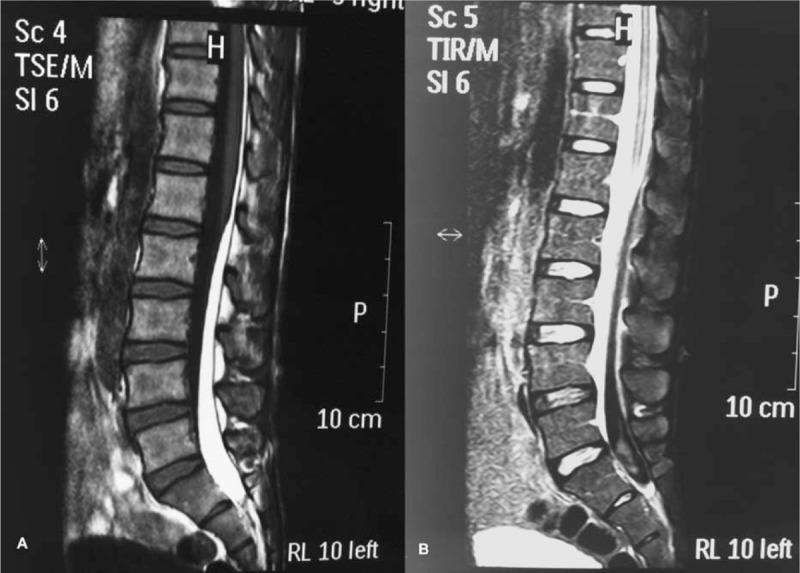

Spontaneous SSDH with ligamentum flavum hematoma was caused by a sudden increase of intravenous pressure, resulting from a marked surge in the intra-abdominal or intrathoracic pressure. Consecutive MRI scans provided valuable information, leading to a diagnosis of spontaneous SSDH. The treatment protocol for spontaneous SSDH should be determined based on the location and stage of the hematoma, as well as the subject's neurological status.

伴有黄韧带血肿的自发性SSDH是由腹内或胸内压力显著升高导致静脉压突然升高引起的。连续的MRI扫描提供了有价值的信息,从而确诊为自发性SSDH。自发性SSDH的治疗方案应根据血肿的位置和阶段以及患者的神经状态来确定。